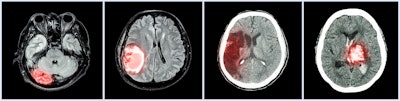

Montin and colleagues used data from the Human Connectome Project-Aging in a study that included T1- and T2-weighted brain images from 716 healthy adults; this data was used to gather 18,324 radiomics features from areas of the brain understood to be highly affected in the course of normal aging: the bilateral hippocampus, the putamen, and the caudate and to train a stacking regressor machine-learning model (a machine-learning technique that combines predictions of multiple estimators, Montin said). The model included eight regressors: Lasso, random forest, k-nearest neighbors, gradient boosting, AdaBoost, HistGradientBoostingRegressor, and MLPRegressor.

The investigators plan to continue this research with muscular sclerosis patients to explore whether the model plus MRI radiomics shows a correlation between brain age and number of brain lesions, according to Montin.